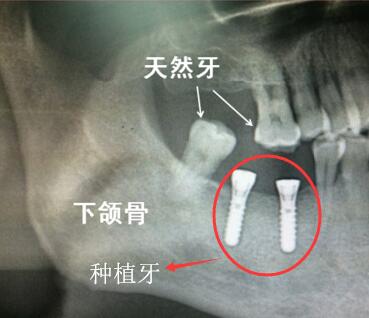

還有,人工牙根通常是植入到牙槽骨裏麵的,肉眼是不可見的,隻是拍片能看到,在牙片上種植牙會(hui) 顯示為(wei) 白色的部分,一般來說,在醫生指導下,大家都能比較準確的判斷出哪顆是種植牙,而且後期複診也主要是根據牙片來判斷種植牙的情況。

做種植牙植入牙根後拍牙片